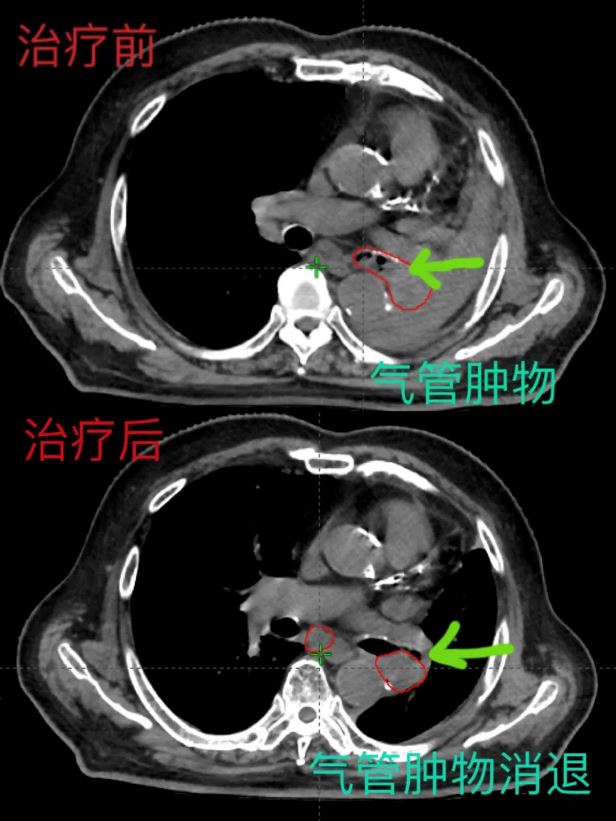

以现代影像技术与放疗技术紧密结合,通过精准的肿瘤定位,精准的计划设计、精准的剂量计算,经过放射治疗10次后,复查胸部CT示:左肺门肿块明显缩小,左主支气管内肿物明显消退,左肺膨胀良好,纵膈回位。左肺呼吸功能恢复。放射治疗疗效显著,患者症状明显改善,有效的减轻了患者的痛苦,提高了生活质量。